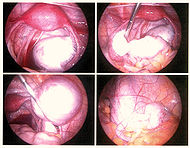

Эндометриоз

Эндометриоз — распространённое гинекологическое заболевание, при котором клетки эндометрия (внутреннего слоя стенки матки) разрастаются за пределами этого слоя. Поскольку эндометриоидная ткань имеет рецепторы к гормонам, в ней возникают те же изменения, что и в нормальном эндометрии, проявляющиеся ежемесячными кровотечениями. Эти небольшие кровотечения приводят к воспалению в окружающих тканях и вызывают основные проявления заболевания: боль, увеличение объема органа, бесплодие. Симптомы эндометриоза зависят от расположения его очагов. Различают генитальный (в пределах половых органов — матки, яичников) и экстрагенитальный (вне половой системы — пупок, кишечник и т. д.) эндометриоз.

По распространению и глубине поражения тканей эндометриозом различают 4 стадии заболевания:

I степень — единичные поверхностные очаги.

II степень — несколько более глубоких очагов.

III степень — множество глубоких очагов эндометриоза, небольшие эндометриоидные кисты одного или обоих яичников, тонкие спайки брюшины.

IV степень — Множество глубоких очагов, большие двусторонние эндометриоидные кисты яичников, плотные сращения органов, прорастание влагалища или прямой кишки.